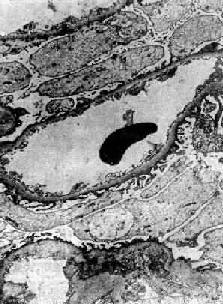

图12-20 轻微病变性肾小球肾炎 电镜下见肾小球毛细血管上皮细胞部分足突消失 肾小管上皮细胞内有多数玻璃样小滴和脂类沉积,是由于肾小球毛细血管通透性增加,大量脂蛋白通过肾小球滤出,而在肾小管被重吸收所致。肾小管腔内可有透明管型。这些变化常与蛋白尿的程度平行。 肉眼观,肾肿胀,体积较大,色苍白。由于大量脂类沉着,切面可见黄色条纹。 【临床病理联系】 脂性肾病病人临床上大多表现为肾病综合征,有大量蛋白尿和严重水肿,与膜性肾小球肾炎不同的是,蛋白尿为高度选择性,主要含小分子蛋白,如白蛋白。肾小球的病变轻微,故一般无血尿和高血压,肾功能也不受影响。 【结局】 大多数病人对皮质激素治疗效果很好,90%以上儿童可以完全恢复,病变在数周内消失。成人预后也很好。少数病人可有反复,一般不发展成慢性。

六、轻微病变性肾小球肾炎(脂性肾病)轻微病变性肾小球肾炎(minimal change glomerulonephrits)的病变特点是在光学显微镜下肾小球无明显变化或病变轻微,故名。由于本病肾小管上皮细胞内常有大量脂质沉积,故又称为脂性肾病(lipoid nephrosis)。临床上常表现为肾病综合征。脂性肾病多见于小儿,成人患者较少,是引起小儿肾病综合征最常见的原因。在小儿肾病综合征中约65%~85%由脂性肾病引起。成人肾病综合征由脂性肾病引起者约占10%~30%。脂性肾病病变可完全恢复,对皮质激素治疗效果很好。 轻微病变性肾炎与其他类型肾炎不同,电镜观察未找到沉积物,免疫荧光检查也未发现肾小球内有免疫球蛋白或补体。其病因和发病机制尚不清楚。有些现象如有些病人在呼吸道感染后发病,或同时伴有其他过敏性疾病,如过敏性鼻炎和湿疹等,提示可能与免疫机制有关。Hodgkin病患者轻微病变性肾炎发病率较高,而已知Hodgkin病患者常有T细胞功能缺陷,故有人认为这种肾炎的发病可能与T细胞功能异常有关。近来有学者提出,肾小球多聚阴离子减少可能是造成本病肾小球毛细血管上皮细胞变化和大量蛋白尿的原因。 【病理变化】 光学显微镜下,肾小球无明显变化或仅有轻度节段性系膜增生。电镜下见弥漫性肾小球脏层上皮细胞足突消失(图12-20),细胞内高尔基器和内质网增多,并可见脂滴。细胞表面常有多数微绒毛形成。足突消失不仅见于脂性肾病,也常见于其他原因引起的大量蛋白尿和肾病综合征。经过治疗或蛋白尿等症状缓解后,脏层上皮细胞的变化可恢复正常。